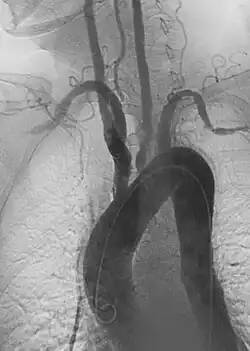

Aortoiliac occlusive disease (Leriche syndrome) is a constellation of symptoms due to significant occlusion of the distal aorta and common iliac arteries, most commonly by atherosclerotic disease The classic symptoms include buttock claudication and erectile dysfunction, with decreased femoral pulses. Additional symptoms of critical limb ischemia can be present. Both surgical and endovascular approaches to revascularization can be considered.

Aneurysm refers to pathologic dilation of an artery to greater than 1.5 times its normal size. True vascular aneurysms are due to degenerative processes in the wall of the artery. Aneurysms can be solitary or multiple and are sometimes found in association with various clinical syndromes, including forms of vasculitis or connective tissue diseases. Aneurysms are typically classified by major shapes, either fusiform (tubular) or saccular (eccentric). Ectasia is another broad term for an enlarged vessel, but is not necessarily pathological. Rupture is a dreaded complication of aneurysms that can lead to extensive, difficult to control bleeding. Aneurysms can also clot, or thrombose, and rapidly occlude the involved vessel, leading to acute distal ischemia.

Aortic aneurysms include thoracic, abdominal and thoracoabdominal aneurysms. Treatment strategies are customized depending on the location, size, rate of growth and extent of the aneurysm as well as the medical comorbidities of the patient. For example, an intact, small but slowly growing aneurysm may be safely monitored with serial imaging for months or years before elective repair is considered. Elective endovascular aortic grafting is now routinely attempted when possible. Endovascular aortic repair (EVAR) refers to treatment of an abdominal aortic aneurysm, while thoracic endovascular aortic repair (TEVAR) is performed on the thoracic aorta. A ruptured aneurysm may be taken emergently for open, endovascular or combination repair.